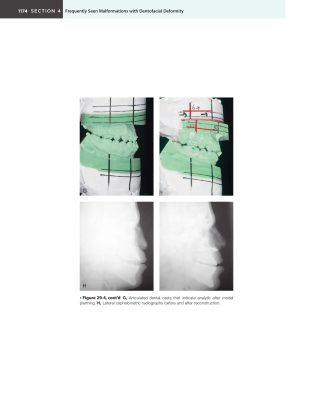

Giới thiệu Lời mở đầu (trang xiii) của các tác giả nhấn mạnh phương pháp…